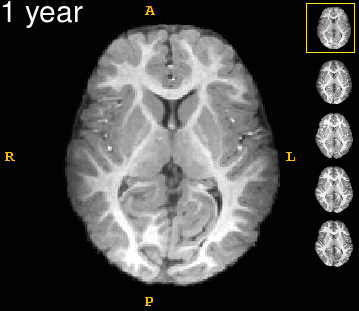

Left: Acquisitions of a single subject with observations at 1, 2, 4, 6, and 8 years old. Right: Sub-cortical structures are segmented for each time point.

Observations in time.gif 8yr with labels.png